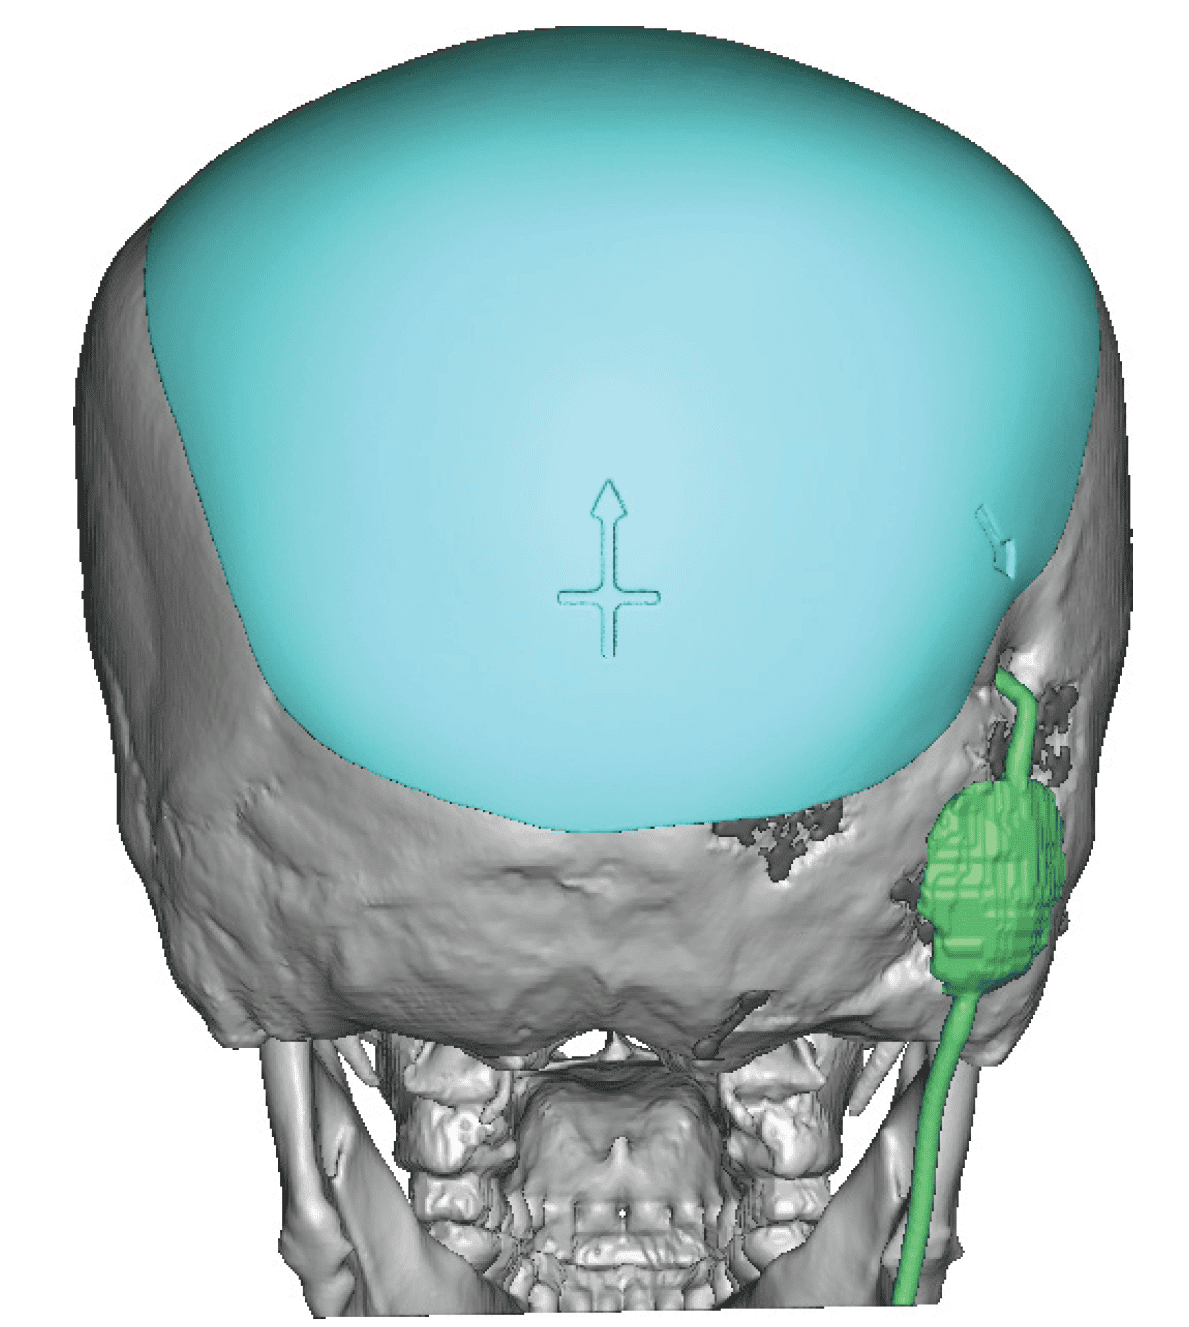

Desire for head shape asymmetry improvement as the final stage of total skull reshaping surgeries. (previous skull implants are in green color)

Placement of custom temporal implant through an incision behind the ear.

Desire for head shape asymmetry improvement as the final stage of total skull reshaping surgeries. (previous skull implants are in green color)

Placement of custom temporal implant through an incision behind the ear.